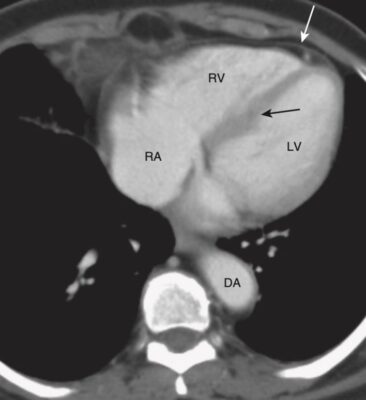

Mức tim thấp (Hình 10)

- Ở mức này, có thể xác định được nhĩ phải, thất phải, thất trái, màng ngoài tim và vách liên thất.

- Tâm nhĩ phải tiếp tục hình thành bờ tim phải. Tâm thất phải nằm ở phía trước, ngay sau xương ức, và thành xô xảm hơn thành tâm thất trái.. Tâm thất trái tạo ra bờ tim trái và bình thường có thành dày hơn tâm thất phải.

- Với thuốc cản quang tĩnh mạch, có thể nhìn thấy vách ngăn liên thất giữa tâm thất phải và trái.

- Màng ngoài tim (pericardium) bình thường dày khoảng 2 mm và thường được bao bọc bởi lớp mỡ trung thất bên ngoài màng tim và lớp mỡ thượng tâm mạc (epicardium) ở bề mặt bên trong của nó.